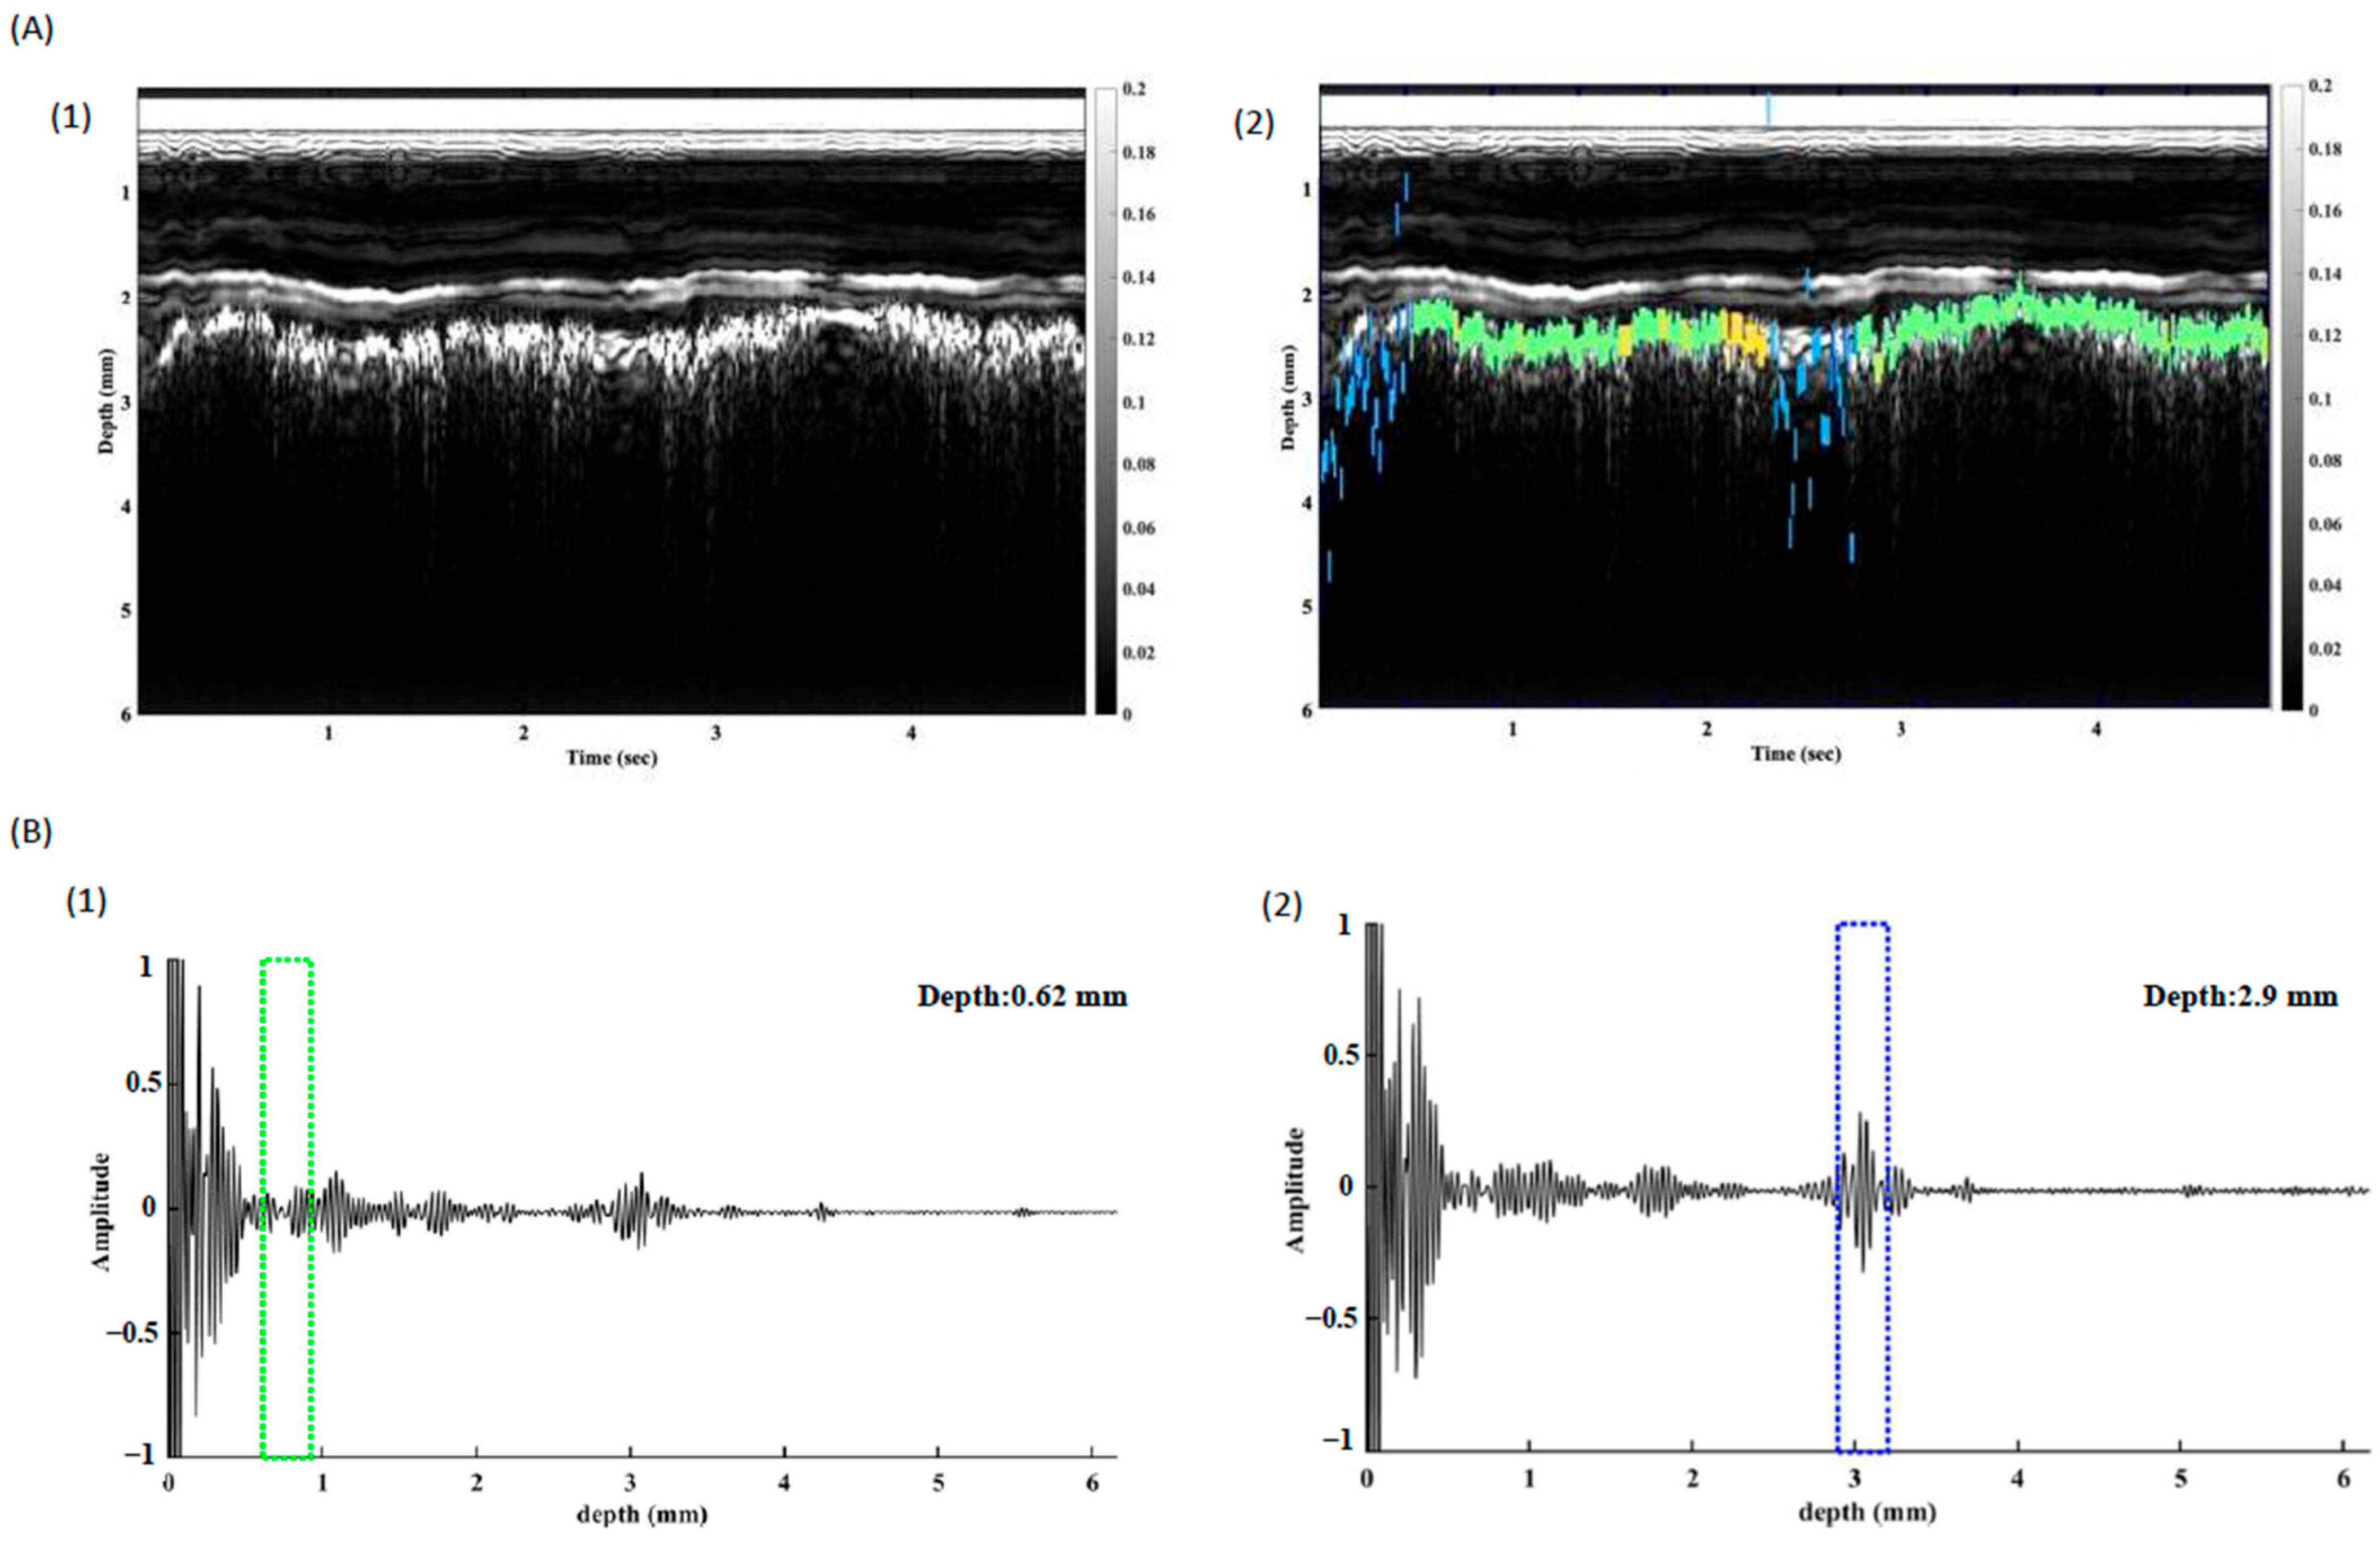

2.5. Time-Frequency Domain Analysis

2.6. In Vivo Study of Pleura Tracking

3. Results